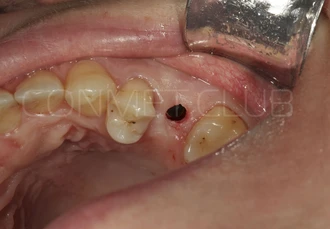

Вид в полости рта пациента перед операцией. С момента удаления зуба 25 прошло 4 месяца. Планируется проведение операции без откидывания слизисто-надкостничного лоскута.

Обязательным условием работы с направляющими шаблонами является проверка точности посадки позиционирующего шаблона на апроксимальные зубы. Посадка не должна быть чрезмерно плотной и шаблон должен располагаться на зубах без баланса.